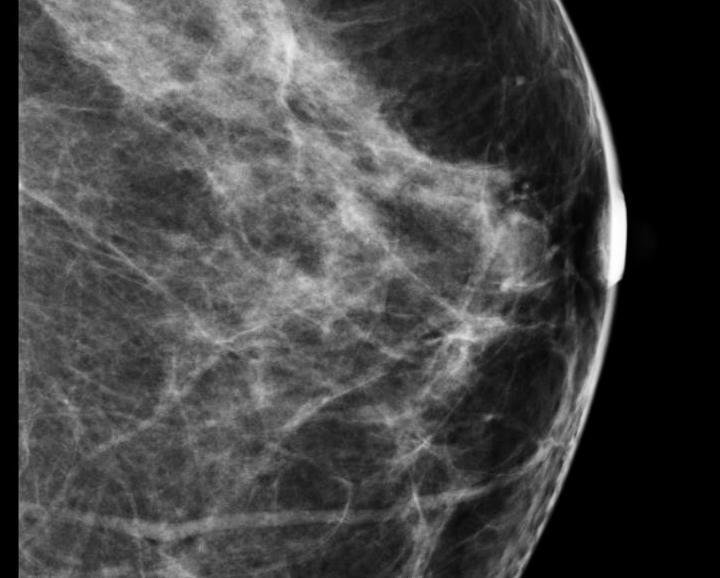

Sept. 10, 2012 – A mammography and women’s health advocacy group, Are You Dense Inc., blasted the American College of Radiology (ACR) and the Society of Breast Imaging (SBI) for their positions on recent research published in the Journal of the National Cancer Institute. The article detailed the risk of death by stage of cancer for women with breast cancer, which Are You Dense said is misleading in its presentation of data to the public.

Sept. 10, 2012 — High mammographic breast density, which is a marker of increased risk of developing breast cancer, does not seem to increase the risk of death among breast cancer patients, according to a study led by Gretchen L. Gierach, Ph.D., of the National Cancer Institute (NCI), part of the National Institutes of Health. The research was conducted in collaboration with investigators from the NCI-sponsored Breast Cancer Surveillance Consortium (BCSC).